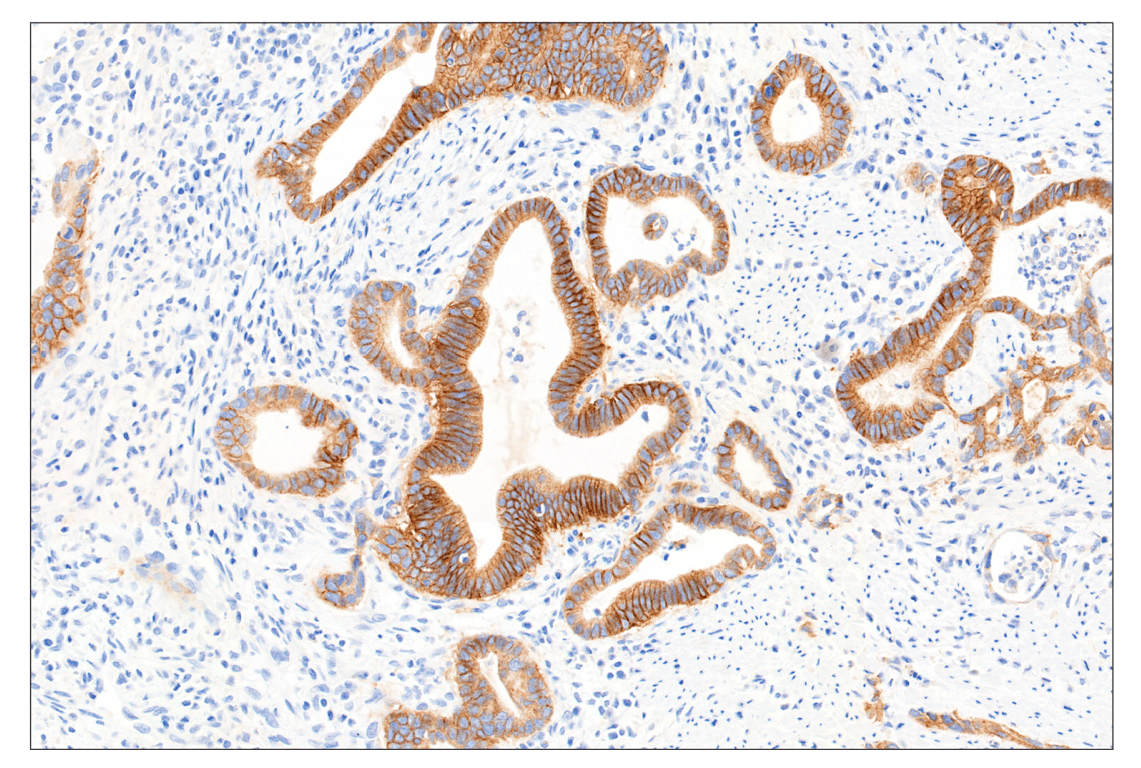

Immunohistochemical analysis of paraffin-embedded human gastric adenocarcinoma using FGF Receptor 2IIIb (FPR2-D) Mouse mAb performed on the Leica BOND RX.

Immunohistochemistry Image 1: FGF Receptor 2IIIb (FPR2-D) Mouse Monoclonal Antibody

Immunohistochemistry Image 2: FGF Receptor 2IIIb (FPR2-D) Mouse Monoclonal Antibody

Immunohistochemistry Image 3: FGF Receptor 2IIIb (FPR2-D) Mouse Monoclonal Antibody